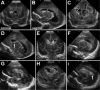

Results: This review summarizes the current knowledge regarding the epidemiology and pathophysiology of IVH and PHH, primarily using evidence-based studies. Advances in obstetrics and neonatology over the past few decades have contributed to a marked improvement in the survival of preterm infants, and neurological morbidity is also starting to decrease. The incidence of IVH is declining, and the incidence of PHH will likely follow. Currently, approximately 15% of preterm infants who suffer severe IVH will require permanent CSF diversion. The clinical presentation and surgical management of symptomatic PHH with temporary ventricular reservoirs (ventricular access devices) and ventriculosubgaleal shunts and permanent ventriculoperitoneal shunts are discussed. Preterm infants who develop PHH that requires surgical treatment remain at high risk for other related neurological problems, including cerebral palsy, epilepsy, and cognitive and behavioral delay. This review highlights numerous opportunities for further study to improve the care of these children.